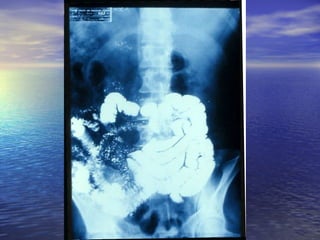

• 1.- CALIBRE: Dilución = obstrucción1.- CALIBRE: Dilución = obstrucción distal, enf.distal, enf.

Celiaca,Celiaca, whipple, linfosarcomawhipple, linfosarcoma

• 2.- ESTENOSIS: Enf. De Crohn, linfosarcoma,2.- ESTENOSIS: Enf. De Crohn, linfosarcoma,

tuberculosis, invasión por tumores cercanostuberculosis, invasión por tumores cercanos

del páncreas, colon.del páncreas, colon.

• 3.- DEFECTOS DE LLENADO: Pólipos ,Sx. Peutz-3.- DEFECTOS DE LLENADO: Pólipos ,Sx. Peutz-

Jegher,Jegher, poliposis familiar, enf. De Crohn, linfomas ypoliposis familiar, enf. De Crohn, linfomas y

metástasis.metástasis.

• 4.- DIVERTICULOSIS: Diverticulosis yeyunal, pseudo-4.- DIVERTICULOSIS: Diverticulosis yeyunal, pseudo-

divertículos (Crohn, esclerosis sistémica)divertículos (Crohn, esclerosis sistémica)